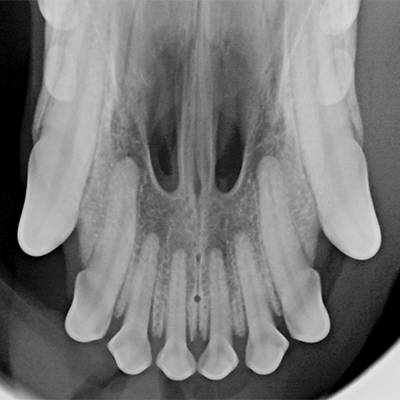

Digital Dental X-Rays

Dental health is a key component of your pet’s overall well-being, and digital dental X-rays are an essential tool for assessing their oral health. At Willow Creek Veterinary Services, our digital dental X-ray system allows us to identify issues below the gum line, such as infections, fractures, or bone loss, that may not be visible during a routine examination. With quick, clear images, we can provide the best treatment options to keep your pet’s smile healthy and bright.